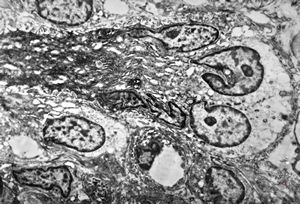

F,41y. | synovial metaplasia - capsule of implantate

F,41y. | synovial metaplasia - capsule of implantate

F,41y. | synovial metaplasia - capsule of implantate

F,41y. | synovial metaplasia - capsule of implantate

F,41y. | synovial metaplasia - capsule of implantate

F,41y. | synovial metaplasia - capsule of implantate

F,41y. | synovial metaplasia - capsule of implantate

F,41y. | synovial metaplasia - capsule of implantate

F,41y. | synovial metaplasia - capsule of implantate